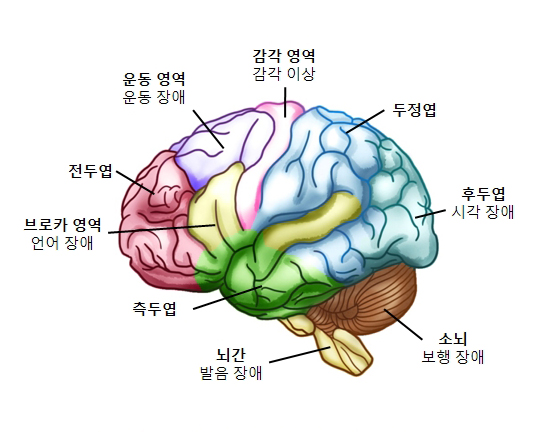

이마엽(전두엽)

대뇌에서 가장 큰 엽을 차지하며 운동과 언어기능을 담당합니다.

관자엽(측두엽)

대뇌의 양쪽에 위치하며 청각 기능을 주로 담당합니다.

마루엽(두정엽)

대뇌의 윗 부분에 위치하며 감각신호를 해석합니다.

뒤통수엽(후두엽)

대뇌의 뒷면에 위치하며 시각기능에 관여합니다.

운동 조절 기능

대뇌 피질에서 운동에 대한 신호를 보내면 이는 뇌줄기와 척수를 지나 필요한 근육으로 전달되어 우리는 원하는대로 몸을 움직일 수 있게 됩니다.

감각인식 및 해석기능

우리 몸의 감각기관에서 들어온 신호를 대뇌의 피질에서 받아들이고 처리하여 느낄 수 있게 해줍니다.

언어전달기능

대뇌 피질에서 수행하며 전두엽의 브로카에서 언어의 발성을, 측두엽의 베르니케 영역에서는 언어의 이해를 담당합니다.